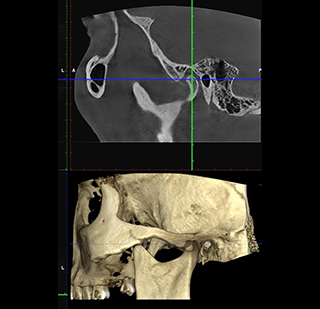

CBCT Scan

Cone beam computed tomography (CBCT) offers 3-D visualization and more accurate imaging compared to conventional radiographs. Radiodent 3D offers precise and focused, small and large view CBCT(Cone beam computed tomography) scans with a very affordable pricing structure depending upon the field of interest.

https://radiant3dxray.com/wp-content/uploads/2025/05/TMJ.jpg

TMJ

Temporomandibular Joint (TMJ) disorders can cause pain, clicking, and restricted jaw movement. Our Double TMJ Scanning feature provides a comprehensive view of both joints simultaneously